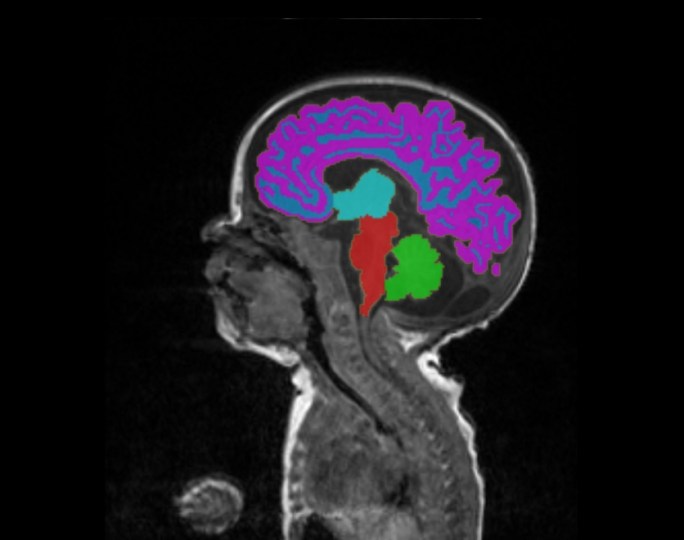

bebe prematuro 1Imagem de ressonância magnética do encéfalo de um bebê recém-nascido com cores diferentes nas diferentes regiões encefálicas. Essa técnica é uma dos várias utilizadas para fazer um mapa do desenvolvimento do cérebro e investigar as causas e consequências de uma lesão cerebral. Fonte da imagem: Universidade de Edimburgo.

Ela descobriu que alimentar os bebês prematuros com leite materno durante o primeiro mês de vida parece estimular o crescimento do córtex cerebral. O córtex é a parte do cérebro que tem muitas funções. Dentre elas, o córtex também é associado à cognição, ou seja, o raciocínio, a ação mental de aquisição de conhecimentos e compreensão através do pensamento, da experiência e dos sentidos. Então, é importante ter mais córtex porque isso pode ajudar também a melhorar o raciocínio e inteligência dessas crianças. Os prematuros em que as dietas diárias eram de pelo menos 50% de leite materno tinham mais tecido cerebral e área da superfície do córtex do que bebês prematuros que consumiram menos leite materno com mesma idade, independentemente se o leite era da própria mãe do bebê ou foi doado por outra mãe. A área de superfície do córtex foi analisada por exames de ressonância magnética.

Uma gravidez a termo, ou seja, no tempo adequado dura 40 semanas. Um nascimento prematuro é considerado quando um bebê nasce antes das 37 semanas de gestação. Como os bebês nascidos prematuramente ainda estavam em desenvolvimento, eles normalmente têm cérebros menores que crianças nascidas a termo e com menor volume e conexões do córtex com outras regiões. O parto prematuro é a principal causa de problemas neurológicos em crianças e tem sido associada a um risco aumentado de alterações psiquiátricas mais tarde na infância.